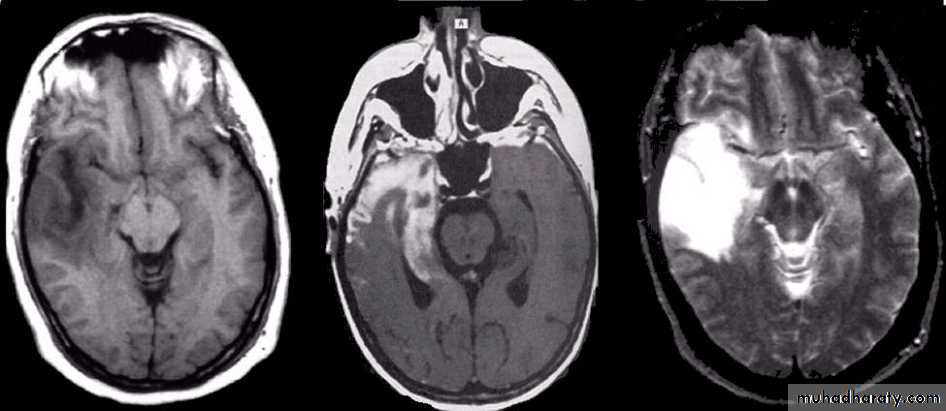

• Retinal lesions consist of two types: mulberry tumors that arise from the nerve head or round and hamartoma• The characteristic brain lesion is a cortical tuber.

• Tubers in the region of the foramen of Monro may cause obstruction of CSF flow and hydrocephalus.• MRI is useful for identification of the lesions.